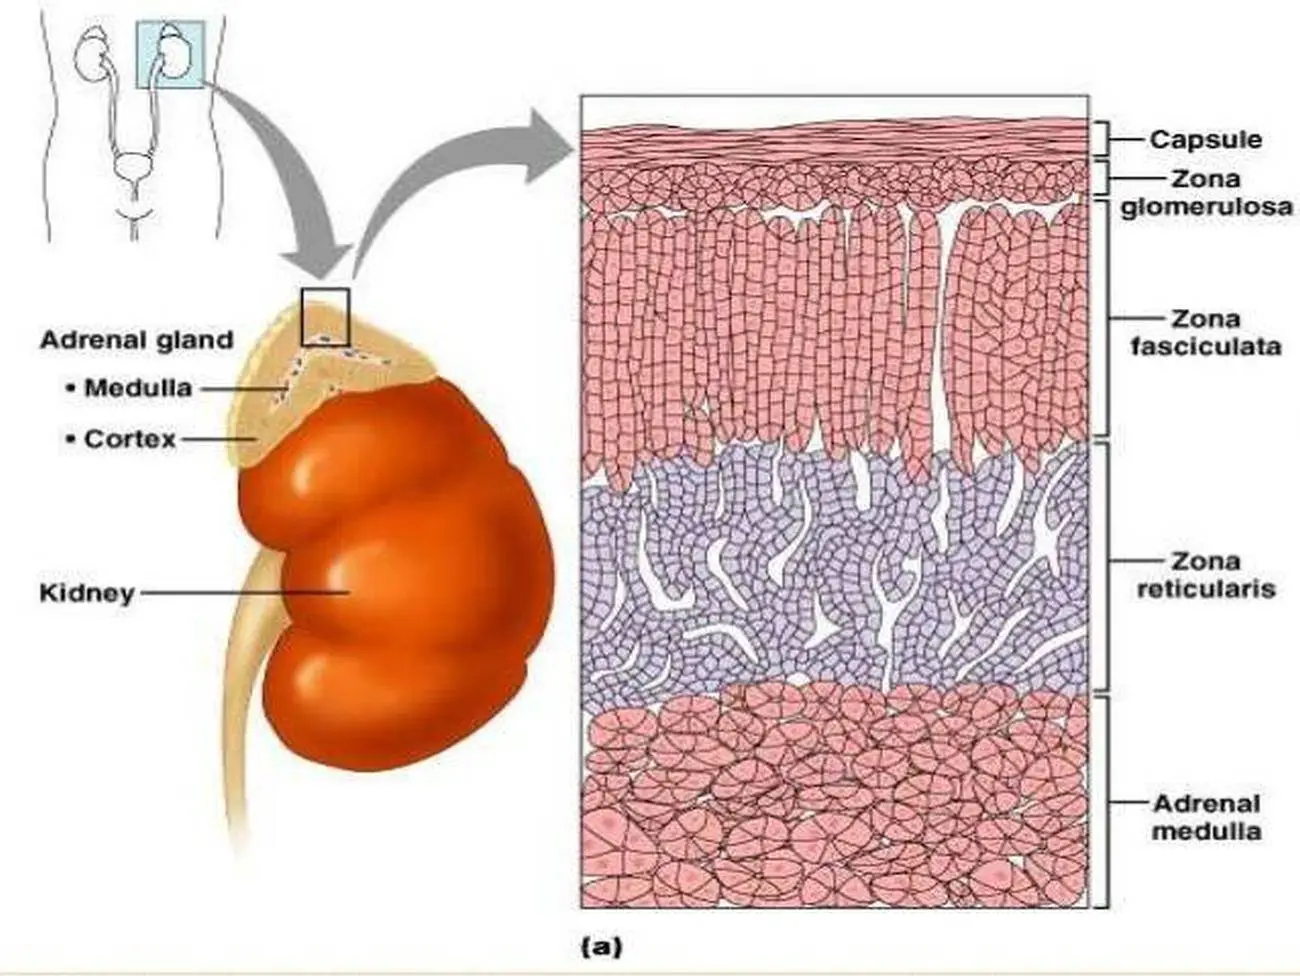

adrenal gland diagram Google Search Biology Diagrams Anatomy . As mentioned, the adrenal glands are two small, roughly triangular glands that sit directly on top of the kidneys. The two major parts of the adrenal gland are the cortex and the medulla. The gland is surrounded by an adipose (fatty) capsule, which acts as a protective barrier. These two major sections of the adrenal are called the adrenal medulla (inner layer), and the adrenal cortex (outer layer). The Adrenal Medulla: The adrenal medulla comes from the neural crest (i.e. embryological basis similar to your central and peripheral nervous systems). It contains homogenous sheets of cells organized into nests.

The adrenal glands consist of the adrenal cortex and medulla, which have distinct, albeit interdependent functional properties. The adrenal cortex contains the zona glomerulosa that produces mineralocorticoids, the zona fasciculata that is the site of glucocorticoid biosynthesis, and the zona reticularis, which is responsible for the production of adrenal androgens. In this chapter, we discuss

The adrenal cortex tends to be fattier and thus has a more yellow hue. The adrenal medulla is more of a reddish-brown color. A thick capsule consisting of connective tissue surrounds the entire adrenal gland. The adrenal cortex is much larger than the smaller medulla, accounting only for approximately 15% of the gland. What is the anatomy of the adrenal cortex? You have two adrenal glands — one on top of each kidney. They contain the cortex, the largest part of the gland, and the medulla, the smaller inner part. Your adrenal gland is highly vascular, with as many as 50 arterial branches providing its blood supply. When does the adrenal cortex develop? Blood first flows through the adrenal cortex and then drains into the adrenal medulla. Adrenal hormones are released into the circulation via the left and right suprarenal veins. Figure 17.6.1 - Adrenal Glands: Both adrenal glands sit atop the kidneys and are composed of an outer cortex and an inner medulla, all surrounded by a connective

Anatomical Structure. The adrenal glands consist of an outer connective tissue capsule, a cortex and a medulla.. Veins and lymphatics leave each gland via the hilum, but arteries and nerves enter the glands at numerous sites.. The outer cortex and inner medulla are the functional portions of the gland. Adrenal Medulla: The hormones secreted by the adrenal medulla are not essential for the survival. Conclusion. Adrenal cortex and adrenal medulla are two major cell layers of the adrenal gland. The adrenal gland is located on the top of the kidney. Both adrenal cortex and adrenal medulla secrete hormones to regulate the functions of the body.